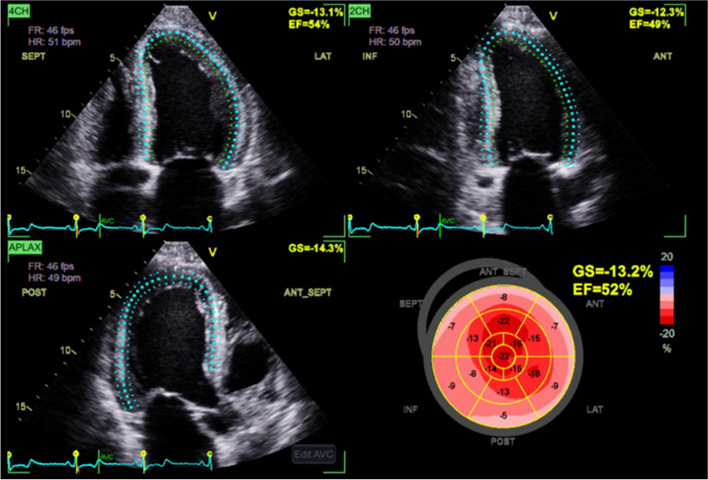

Background: Global longitudinal strain (GLS) is a useful marker for the echocardiographic evaluation of left ventricular (LV) systolic dysfunction. Presently GLS is derived from speckle tracking of LV images, but speckle tracking software is not always available. We seek to determine if manually measured GLS (MM-GLS) by assessing mid-myocardial lengths can be a reliable alternative to speckle tracking GLS (ST-GLS).

Methods: Transthoracic echocardiogram images of a tertiary hospital in Australia were retrospectively analyzed to study the relationships between ST-GLS, MM-GLS, and LV ejection fraction (LVEF). We further evaluated the impact of image quality and regional wall motion abnormalities on those relationships.

Results: Echocardiography studies from 154 patients were included (female sex, 36%; mean age, 61.7 ± 14.8 years). The average LVEF was 51.3% ± 11.3% and the average ST-GLS was 16.7 ± 3.8. MM-GLS strongly correlated with ST-GLS (intraclass correlation coefficient, 0.986; P < 0.001) and with LVEF regardless of the presence of regional wall motion abnormalities. If using GLS cutoff of more than 18% as normal, 97.5% of studies with normal ST-GLS had normal MM-GLS. If using GLS cutoff as less than 16% as abnormal, 95.5% of studies with abnormal ST-GLS had abnormal MM-GLS. There was no case with ST-GLS > 18% and MM-GLS < 16%, nor were there any case in with ST-GLS < 16% and MM-GLS > 18%.

Conclusions: MM-GLS correlates strongly with ST-GLS. If ST-GLS cannot be accurately assessed, MM-GLS may be a useful alternative to provide GLS values in both clinical and research studies.